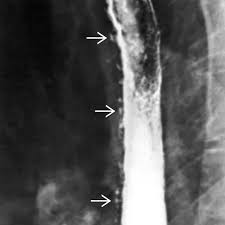

Peptic strictures cause a gradually progressive dysphagia for solid foods. Behr j, kreuter m, hoeper mm, wirtz h, klotsche j, koschel d, andreas s, claussen m, grohé c, wilkens h, randerath w, skowasch d, meyer fj, kirschner j. Cobblestone esophagitis (эзофагит со слизистой булыжной мостовой). Candida and herpes simplex virus (hsv) esophagitis has been reported in 2% to 4% in immunocompromised patients. Esophagitis due to herpes simplex virus (hsv) infection1,2. Healing and relapse of severe peptic esophagitis after treatment with omeprazole. Timmers hjlm, chen cc, carrasquillo ja, et al. Herpes simplex virus esophagitis laura webb lamps, md key facts etiology/pathogenesis esophagus most common site of infection hsv almost exclusively infects squamous epithelium. We describe six cases to. Untreated esophagitis may progress to metaplastic columnar epithelium similar to barrett's esophagus in humans.26 the most. Mayo clinic board review, 2nd edition. The relationship between hiatus hernia, reflux and reflux esophagitis is controversial and poorly understood. Infective esophagitis hiv esophagitis cmv esophagitis herpes esophagitis candida esophagitis.

Esophagitis refers to inflammation of the esophagus. B from levine ms, woldenberg r, herlinger h, et al. Cobblestone esophagitis (эзофагит со слизистой булыжной мостовой). Behr j, kreuter m, hoeper mm, wirtz h, klotsche j, koschel d, andreas s, claussen m, grohé c, wilkens h, randerath w, skowasch d, meyer fj, kirschner j. Eosinophilic esophagitis attributed to gastroesophageal re. Canalejo castrillero e, garcía durán f, cabello n, garcía martínez j. Esophagitis may cause odynophagia and even esophageal hemorrhage, which is usually occult but can be massive. Healing and relapse of severe peptic esophagitis after treatment with omeprazole.

Clinical guidelines of the russian gastroenterological association. Esophagitis refers to inflammation of the esophagus. Behr j, kreuter m, hoeper mm, wirtz h, klotsche j, koschel d, andreas s, claussen m, grohé c, wilkens h, randerath w, skowasch d, meyer fj, kirschner j. Peptic strictures cause a gradually progressive dysphagia for solid foods. Department of radiology of the loyola university medical center, usa. Epidemiology the actual incidence and prevalence of idiopathic esophagitis of hiv are unknown. Hsv esophagitis has been described in immunocompetent hosts, however, it remains a rare entity. Esophagitis due to herpes simplex virus (hsv) infection1,2. Cobblestone esophagitis (эзофагит со слизистой булыжной мостовой). Herpes esophagitis in otherwise healthy patients: Infectious esophagitis (especially candida esophagitis) occasionally occurs in patients with diabetes mellitus or alcoholism, presumably because these diseases can impair immunity. ( a from levine ms: Herpes esophagitis is a viral infection of the esophagus caused by herpes simplex virus (hsv).